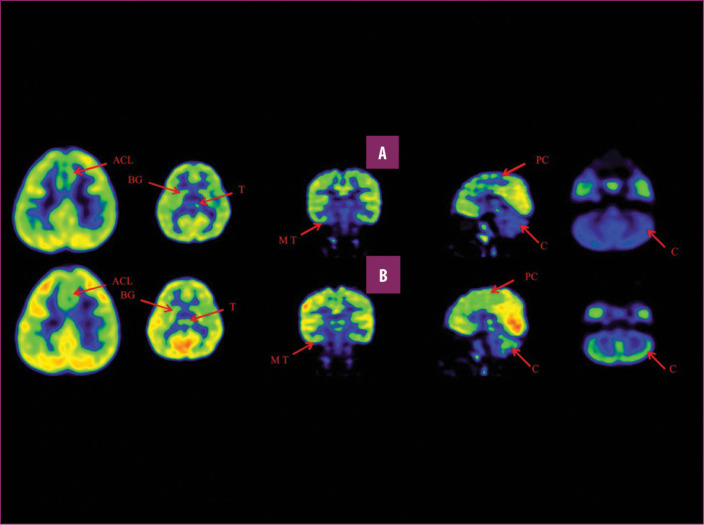

前扣带回 (ACL)、顶叶皮层 (PC)、内侧颞叶皮层 (MT)、基底神经节 (BG)、丘脑 (T) 和小脑 (C)。B 行)第一次移植后6个月后PETCT脑部扫描的干预后图像显示标记区域有所改善。蓝色代表代谢减退区域。绿色代表正常的新陈代谢区域。图A和B的比较显示蓝色区域显着减少,绿色区域增加,这表明大脑的新陈代谢得到改善。

与之前的情况相比,他在矢状面和额状面上的体重变化有所改善;头部、躯干和骨盆的排列也得到改善,双侧腿筋和小腿肌肉的紧绷感也有所减轻。患者开始执行双手任务。在认知方面,由于他定期上学,他的注意力持续时间和久坐耐力也得到了改善。GMFM评分从60.67提高到67.75;GMFCS等级由Level3提升至Level2;和FIM评分从97分提高到99分。在比较第一次细胞治疗之前和之后七个月期间进行的脑部PETCT扫描结果时,前扣带叶、顶叶皮层、内侧颞叶皮层、丘脑、基底神经节和小脑(表格1)。